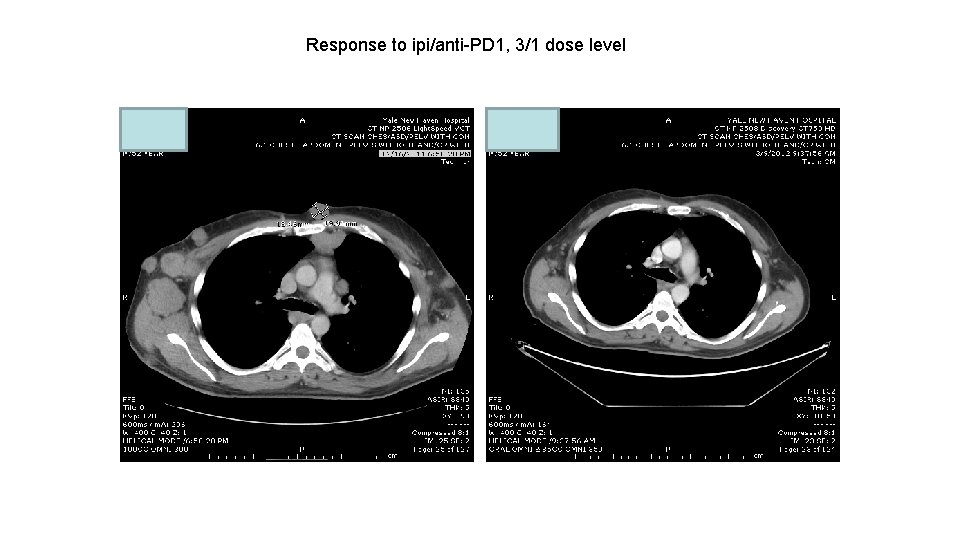

Response to ipi/anti-PD 1, 3/1 dose level